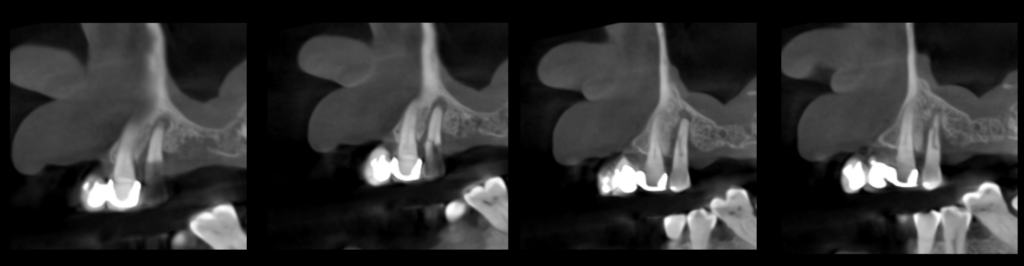

En la tomografía computarizada de haz cónico (CBCT) de ambos maxilares, evaluada mediante cortes axiales (Figura 2), transaxiales (Figura 3) y tangenciales (Figura 4), se observó una línea hipodensa de trayecto sinuoso que se extendía desde la superficie cervicovestibular hacia el tercio apical radicular palatino, comprometiendo el conducto radicular. Asimismo, se evidenció un proceso osteolítico perirradicular y pararradicular en el tercio medio radicular palatino, que ocasionaba adelgazamiento de la cortical de la tabla ósea.

CORTES TRANSAXIALES

CORTES TANGENCIALES